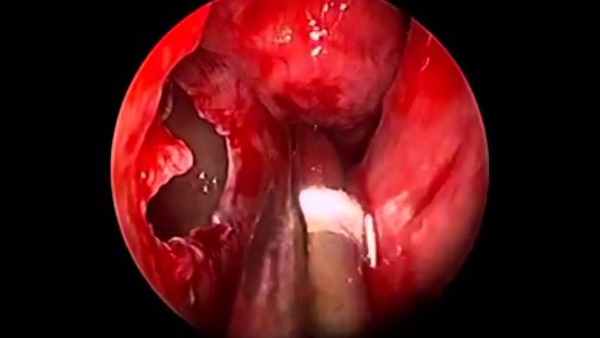

ΕΝΔΟΣΚΟΠΙΚΗ ΧΕΙΡΟΥΡΓΙΚΗ ΡΙΝΟΣ – ΠΑΡΡΙΝΙΩΝ

ΧΕΙΡΟΥΡΓΙΚΗ ΡΙΝΙΚΩΝ ΚΟΓΧΩΝ